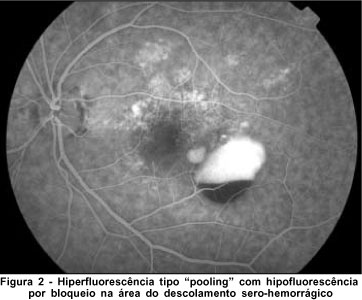

Paciente de 54 anos, sexo masculino, pardo, natural e procedente de Fortaleza, procurou nosso serviço com queixa de baixa acuidade visual súbita em olho direito (OD). Era portador de hipertensão arterial sistêmica. Ao exame oftalmológico, apresentava: acuidade visual de percepção luminosa em OD e 20/25 em olho esquerdo (OE), segmento anterior sem anormalidades e pressão intra-ocular de 12 mmHg em ambos os olhos (AO). Ao exame fundoscópico: hemorrragia vítrea em OD e em OE drusas moles em pólo posterior. Ao exame ultra-sonográfico: imagem sugestiva de hemorragia vítrea com retina aplicada. Após três meses, o paciente foi submetido a vitrectomia via pars plana (VVPP), quando foi constatada a presença de cicatriz disciforme em região macular. Paciente evoluiu com descolamento de retina e perda de visão em OD. Após cinco meses de acompanhamento, foi observado descolamento sero-hemorrágico do epitélio pigmentário da retina (EPR) em OE (Figura 1). Exame angiofluoresceinográfico: hiperfluorescência com impregnação tardia correspondendo a drusas e hiperfluorescência tipo "pooling" na área do descolamento seroso com hipofluorescência por bloqueio secundária a hemorragia (Figura 2). A indocianinografia demonstrou alterações vasculares com estruturas polipoidais na margem nasal do descolamento do epitélio pigmentário (Figura 3). Após um período de cinco meses, o paciente mostrou involução da vasculopatia em OE (Figuras 4 e 5), permanecendo com visão de 20/25.